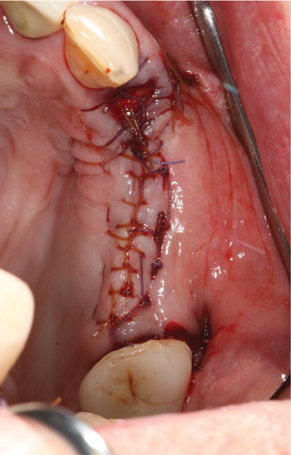

Fig 13. Flap closure and suturing after graft and membrane placement at maxillary left quadrant.

Figure 13